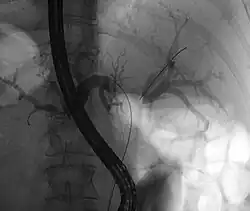

Klatskin tumor during ERCP. Wires were inserted into the left and right biliary systems. Both parts were injected through a tube with contrast, but there is no contrast visible in the area of confluence of the two systems